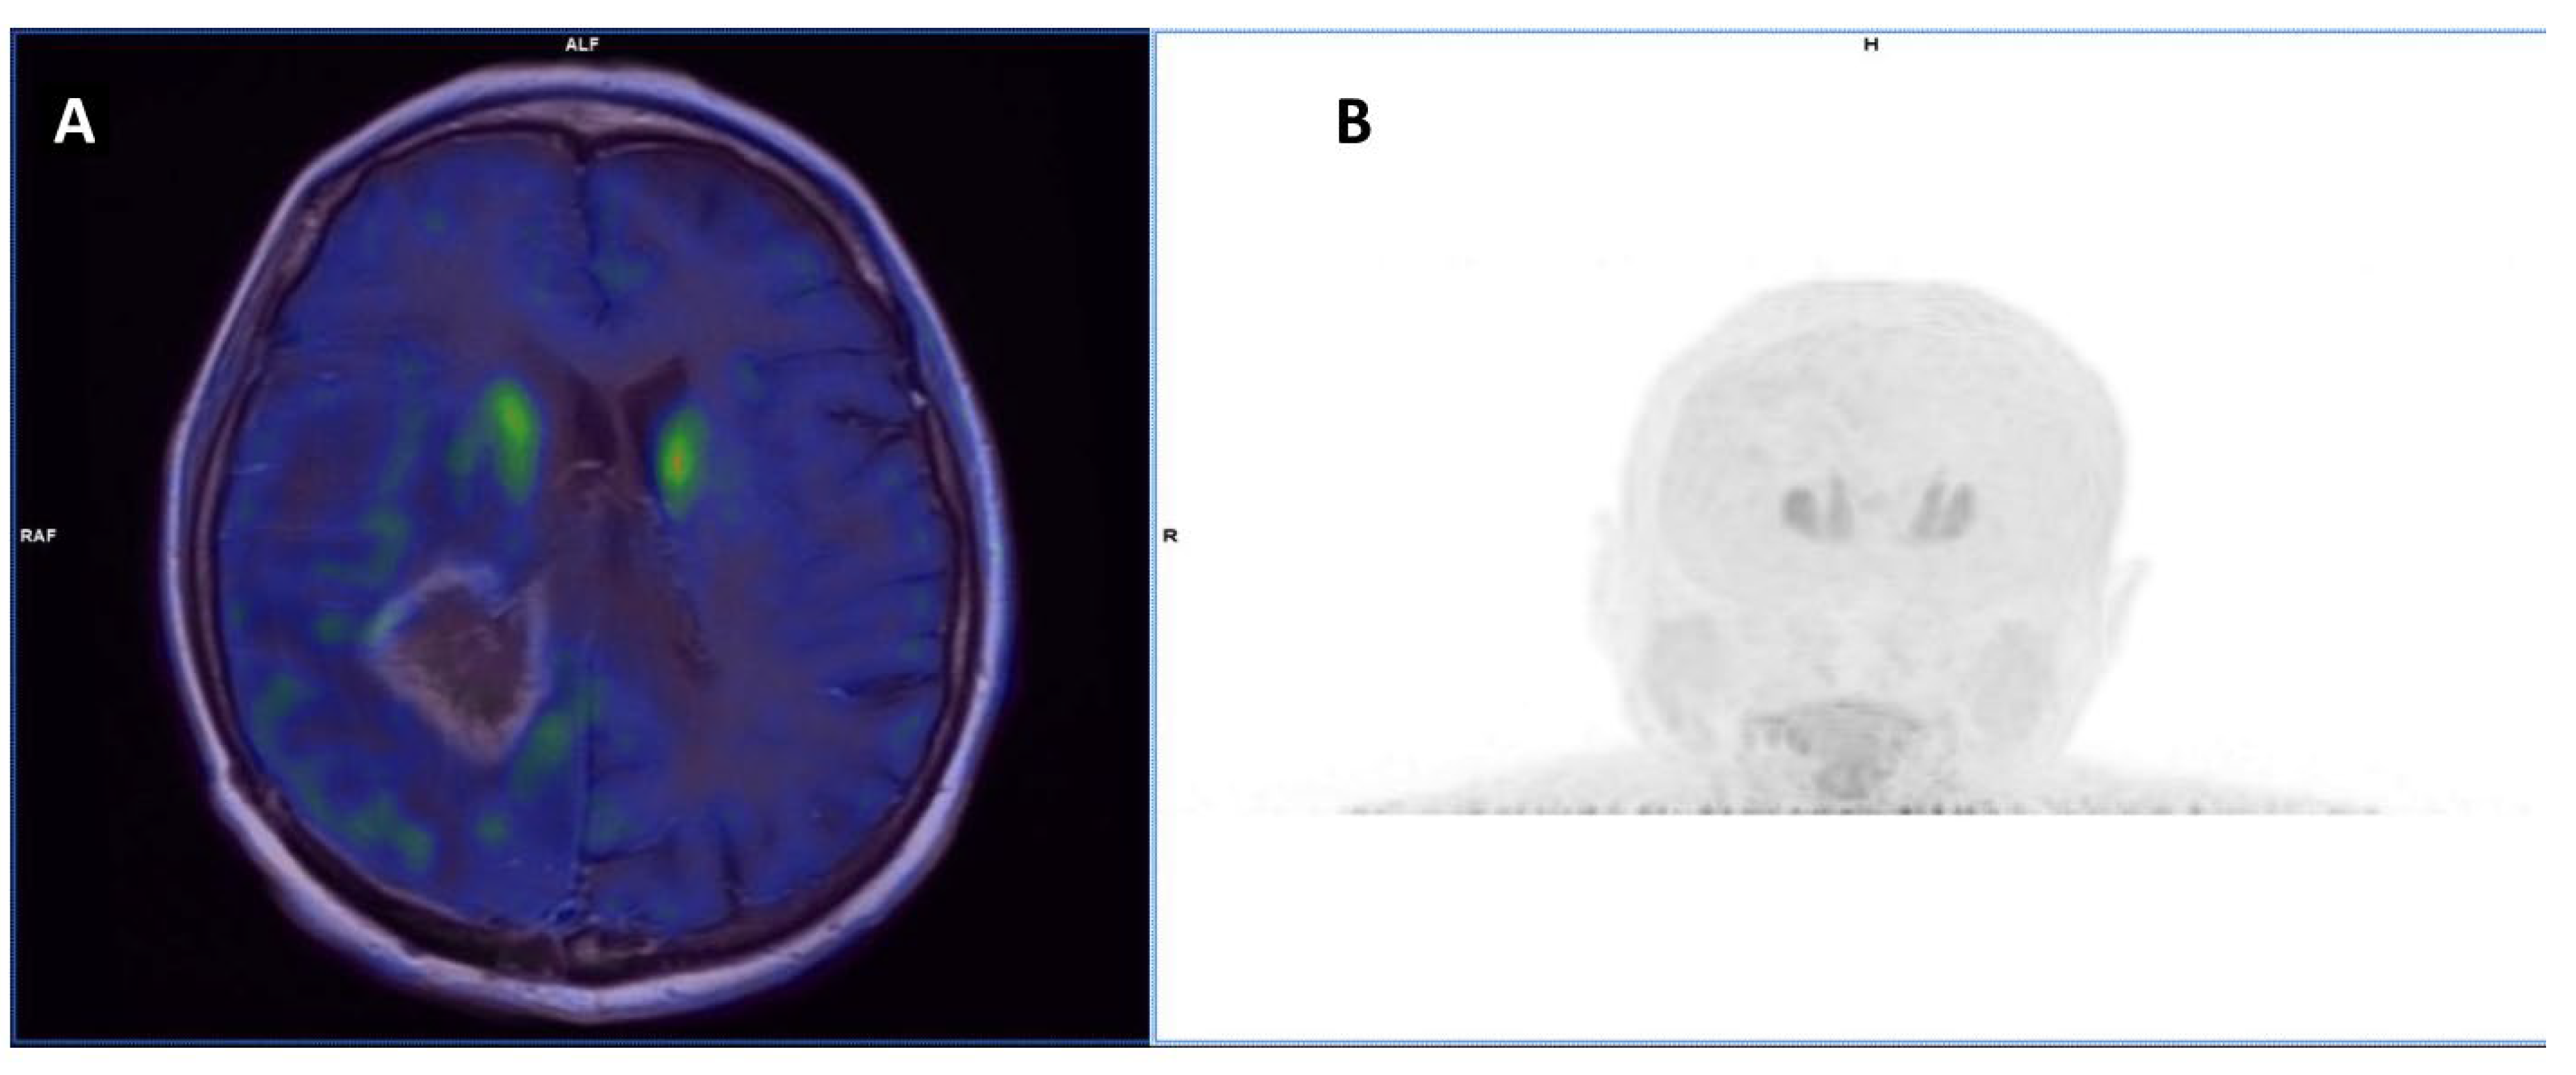

- Lohmann, P.; Kocher, M.; Ruge, M.I.; Visser-Vandewalle, V.; Shah, N.J.; Fink, G.R.; Langen, K.-J.; Galldiks, N. PET/MRI Radiomics in Patients with Brain Metastases. Front. Neurol. 2020, 11, 1. [Google Scholar] [CrossRef]

- Lohmann, P.; Kocher, M.; Ceccon, G.; Bauer, E.K.; Stoffels, G.; Viswanathan, S.; Ruge, M.I.; Neumaier, B.; Shah, N.J.; Fink, G.R.; et al. Combined FET PET/MRI Radiomics Differentiates Radiation Injury from Recurrent Brain Metastasis. NeuroImage Clin. 2018, 20, 537–542. [Google Scholar] [CrossRef]

- Lohmann, P.; Stoffels, G.; Ceccon, G.; Rapp, M.; Sabel, M.; Filss, C.P.; Kamp, M.A.; Stegmayr, C.; Neumaier, B.; Shah, N.J.; et al. Radiation Injury vs. Recurrent Brain Metastasis: Combining Textural Feature Radiomics Analysis and Standard Parameters May Increase (18)F-FET PET Accuracy without Dynamic Scans. Eur. Radiol. 2017, 27, 2916–2927. [Google Scholar] [CrossRef]